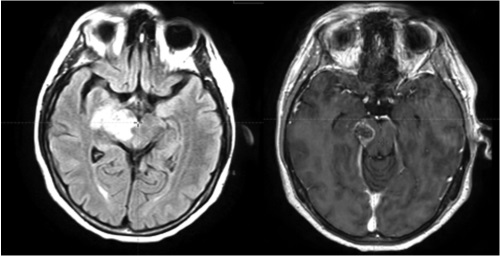

Введение. При глиомах ствола мозга медиана общей выживаемости составляет от 6 до 16 месяцев. Существующие подходы к лечению глиом стволовой локализации не показали значимого улучшения выживаемости, поэтому особенно актуален вопрос поиска новых лечебных стратегий. Материалы и методы. В радиотерапевтическом отделении № 1 БУЗ ВО «ВОНКОЦ» проходила лечение пациентка с диагнозом: глиома grade 4 правого таламуса, заднего бедра внутренней капсулы, правой ножки мозга. Диагноз выставлен клинико-рентгенологически. Тактика лечения: лучевая терапия до СОД 60 Гр: РОД 2 Гр с темозоломидом. Результаты. Проведен курс химиолучевого лечения: дистанционная лучевая терапия по методике IMRT совместно с приемом темозоломида 75 мг/м² /сут. Предписанная доза для пораженной области вне ствола составила 60 Гр, для области, включающей ствол мозга,— 56 Гр. Переносимость лечения была удовлетворительной. Явлений токсичности и прогрессирования неврологического дефицита не отмечалось. Обсуждение. По данным большинства научных исследований, лучевая терапия с СОД 54 Гр — проверенный терапевтический вариант при лечении глиом стволовой локализации. Есть исследования, показывающие, что максимальная толерантная доза на ствол мозга может быть увеличена до 64 или 69,59 Гр. Таким образом, выбор предписанной дозы в рассмотренном клиническом случае выглядит несколько заниженным. Однако в процессе планирования была поставлена задача добиться однородного дозового распределения. В дальнейшем при первичных образованиях ствола мозга видится целесообразным использование 58 Гр в качестве предписанной дозы при соблюдении прочих необходимых критериев. Заключение. В рассмотренном клиническом случае становится возможным подведение суммарной дозы 56–60 Гр на значительный объем опухоли ствола мозга с учетом имеющихся критериев толерантности с достижением удовлетворительного покрытия дозой и отсутствием развития серьезных неврологических осложнений у пациента в ходе лечения.